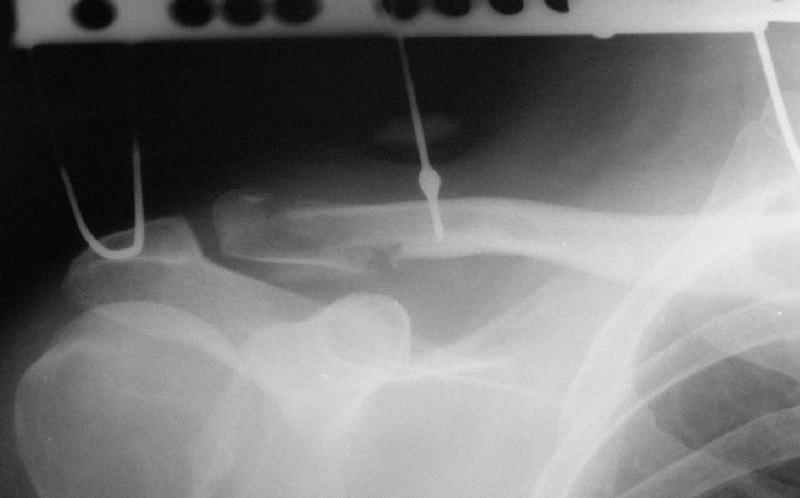

Сегодня прооперировал больного - накостный остеосинтез реконструктивной пластиной с ааллотендопластикой кл-кл связки.

На операции - обширная межотломковая ткань - мобилизовал проксимальный отломок без иссечения м-отломк.ткани, резекция выступающего конца( в последующем использовал как трансплантат).

Однако, я сомневаюсь в правильности выбора метода фиксации - фактически только 1 винт (на акромиальном отростке) является рабочим и мне кажется зря вы не убрали рубцы из зоны перелома - для костного сращения контакт кость-кость вроде бы как желателен.

Время покажет, не мигрировал бы только этот самый рабочий винт из губчатой кости....

После мобилизации проксимального отломка достигнут контакт в нижней части . 2 винта в дистальном отломке + петля аллосухожилия, проведенная через канал в проксимальном отломке должна нейтрализовать смещающие силы - надеюсь.